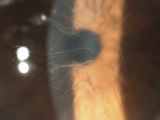

角膜変性症はレーシックを受けると、角膜が白く濁るなど、視力が低下する病気です。眼科専門医の診断でも、角膜変性症未発症の遺伝子保持者の診断は不可能です。アベリーノユニバーサルテストでは、角膜変性症を100%見つけることができます。最近”角膜変性症の診断をしている”と他のクリニックで宣伝をしているようです。角膜変性症は遺伝子疾患ですので、DNA検査を行わない角膜変性症の診察は確実に診断することができません。当院ではこの認定証をアベリーノ社より頂いておりますので、安心してレーシックを受けて頂けることができます。

眼科専門医の診察でも角膜変性症未発症の遺伝子保持者の診断は不可能なため、当院は「臨床試験結果、特異度・敏感度共に100%」、唯一無二のアベリーノユニバーサルテストを導入しています。角膜変性症は、症状が進行した場合視力の大幅な低下に繋がります。

また角膜移植後も再発する疾患です。当院では患者様に安心・安全にレーシックを受けて頂く必須の

検査をしています。